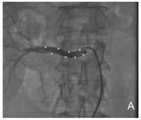

前述のMahfoud et al.の糖尿病研究において、以下の特定のアブレーションプロトコルに従った:腎二重曲線(renal double curve)あるいは左内胸動脈ガイディングカテーテルを使用して、処置カテーテルを各腎動脈へ挿入し、それぞれ最大で2分間続く高周波アブレーションを8ワットの低電力で適用して、各腎動脈内で長手方向と回転方向に分離された最大で6つの切除された部分を得た。第1の遠位の腎大動脈分岐から小孔へと処置を行った。カテーテル先端のインピーダンスと温度は絶えずモニタリングし、あらかじめ決められたアルゴリズムに従って高周波エネルギー送達を調節した。 The aforementioned Mahfood et al. In the diabetes study of, the following specific ablation protocols were followed: using a renal double curve or a left internal thoracic guiding catheter, a treatment catheter was inserted into each renal artery, each up to a maximum. High frequency ablation lasting 2 minutes was applied at a low power of 8 watts to obtain up to 6 excised sections in each renal artery separated longitudinally and rotationally. Treatment was performed from the first distal renal aortic bifurcation to the small foramen. Impedance and temperature at the tip of the catheter were constantly monitored and high frequency energy delivery was regulated according to a predetermined algorithm.

アブレーションを行うことができるようになる前は腎神経構造が最優先の検討課題であるが、除神経のためのカテーテル挿入を企図することができるようになる前は、個々の腎臓の構造を注意深く検討しなければならない。Krum et al./Esler et al.の研究に関して明記されたように、カテーテル挿入の適格性は、腎動脈の解剖学的形態、腎動脈狭窄症、従来の腎臓ステント挿入あるいは血管形成術、および二重腎動脈(dual renal arteries)の評価によって判定された。異常な、または普通でない腎臓構造がカテーテル挿入にとっての障害となるだけでなく、とりわけ、適応外のカテーテルシステム(つまり、それ自体が腎動脈のアブレーションのために特別に設計されたものではないカテーテル)が使用される場合、腎臓構造の正常な変化も課題であると判明することがある。最適以下のカテーテルシステムを用いる腎臓のカテーテル挿入の危険は、繊細な組織を通るこうしたカテーテル先端の雑なまたはギクシャクとした操作を原因とする腎動脈の破裂、過度のアブレーションエネルギーを適用したことを原因とする動脈壁または腎動脈内皮の破裂または損傷、および動脈の解剖を含むこともある。したがって、多くの適格の難治性患者集団が処置されるように、腎臓の構造と腎臓の構造内の共通する異常のために特別に設計されたカテーテルシステムが望ましい。 Before ablation is possible, renal neural structure is a top priority, but before catheter insertion for denervation can be planned, individual renal structure should be carefully examined. Must be considered. Krum et al. / Esler et al. Eligibility for catheter insertion includes anatomical morphology of the renal arteries, renal artery stenosis, conventional renal stenting or angioplasty, and dual renal arteries. It was judged by evaluation. Not only are abnormal or unusual renal structures an obstacle to catheter insertion, but above all, catheter systems that are not indicated (ie, catheters that are not themselves specifically designed for renal artery ablation). When is used, normal changes in renal structure may also prove to be a challenge. The danger of renal catheterization using a suboptimal catheter system is due to the application of rupture of the renal arteries, excessive ablation energy, due to the rough or jerky manipulation of these catheter tips through delicate tissue. It may also include rupture or damage to the arterial wall or renal artery endothelium, and arterial dissection. Therefore, a catheter system specifically designed for common abnormalities within the structure of the kidney and the structure of the kidney is desirable so that many eligible intractable patient populations are treated.